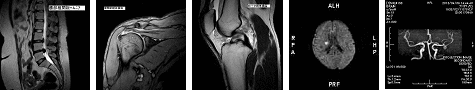

〇MRI検査(オープン型MRI)

*オープン型MR

・ オープン型MRI最上位機種を導入1テスラに匹敵する画像が得られます。

・ オープン型MRIは広く開放的な環境にて検査を受けられますので、狭いところが苦手な方や小児やお年寄りなど、MRI検査か苦手な方にも配慮しています。

・ DWI撮影による急性期脳梗塞診断やMRAによる脳血管・頚動脈などの血管病変の検査が可能です。